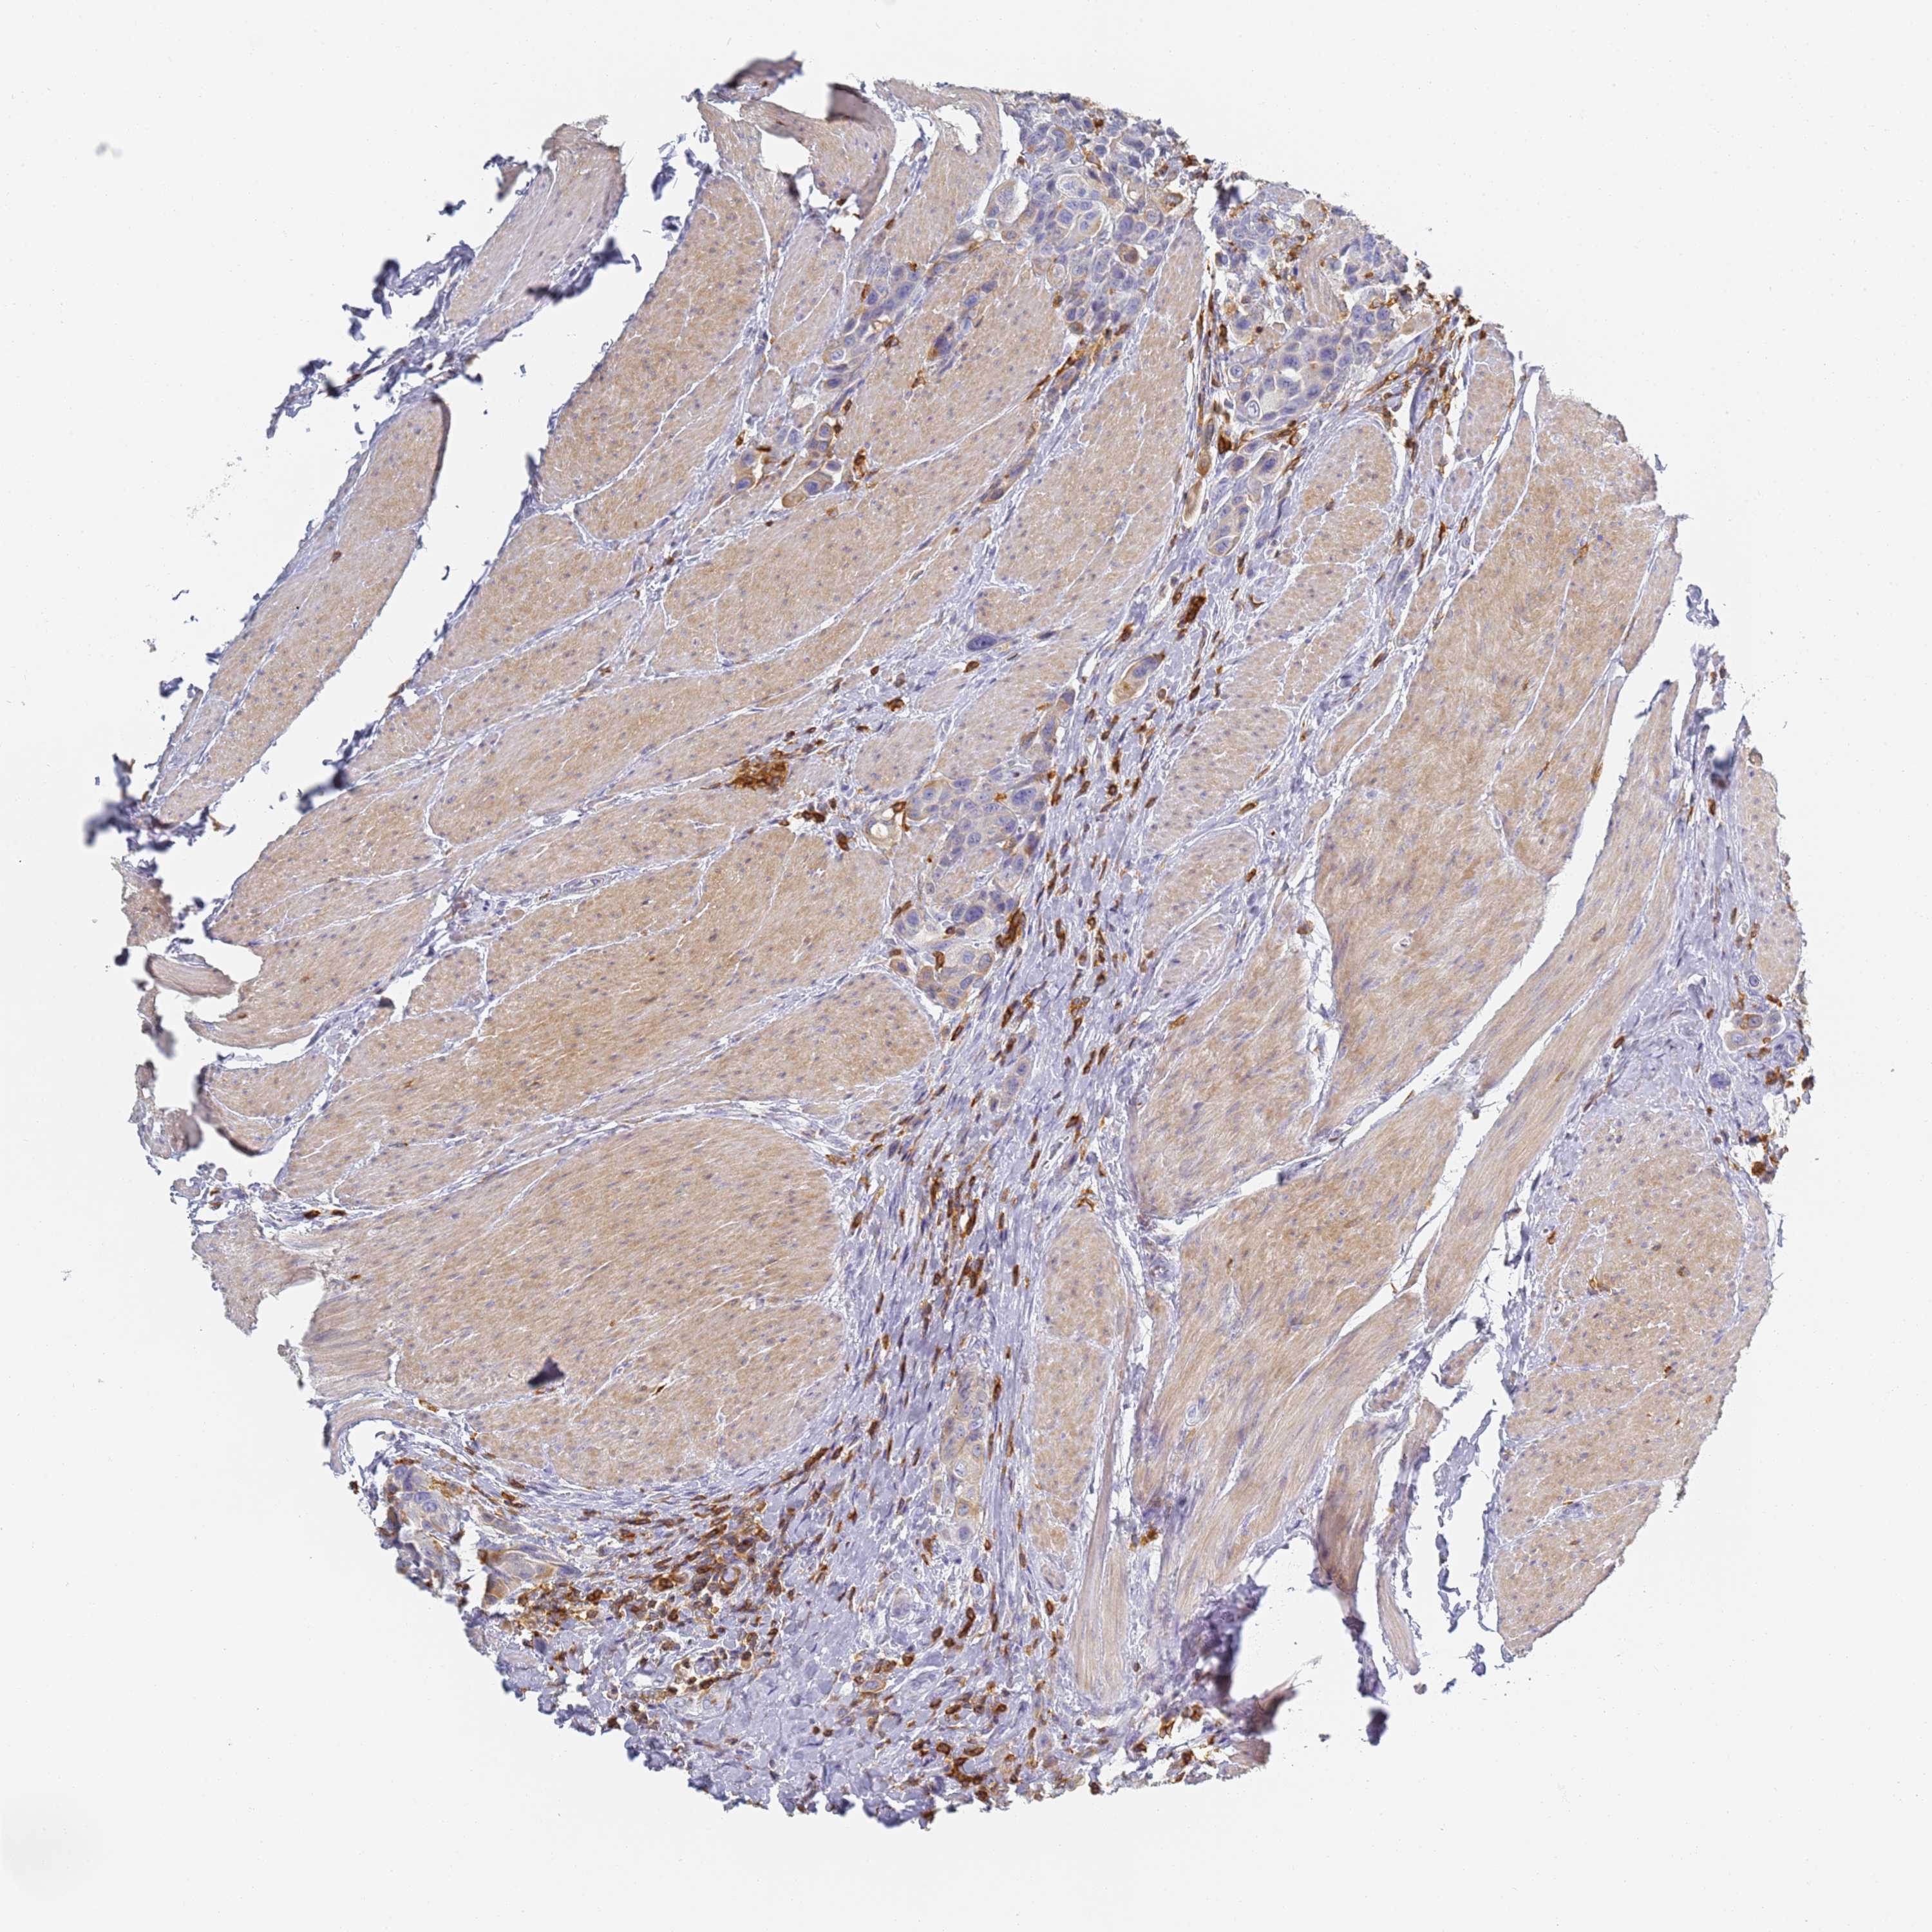

UROTHELIAL CANCER - Protein expressioni

A mouse-over function shows sample information and annotation data. Click on an image to view it in a full screen mode. Samples can be filtered based on level of antibody staining by selecting one or several of the following categories: high, medium, low and not detected. The assay and annotation is described here.

Antibody stainingi

Antibody staining in the annotated cell types in the current human tissue is reported as not detected, low, medium, or high, based on conventional immunohistochemistry profiling in selected tissues. This score is based on the combination of the staining intensity and fraction of stained cells.

Each image is clickable and will lead to virtual microscopy that enables deeper exploration of all samples and also displays staining intensity scores, fraction scores and subcellular localization as well as patient and tissue information for each sample.

Antibody HPA038666

Antibody HPA038667

Urothelial carcinoma, High grade

Urothelial carcinoma, Low grade